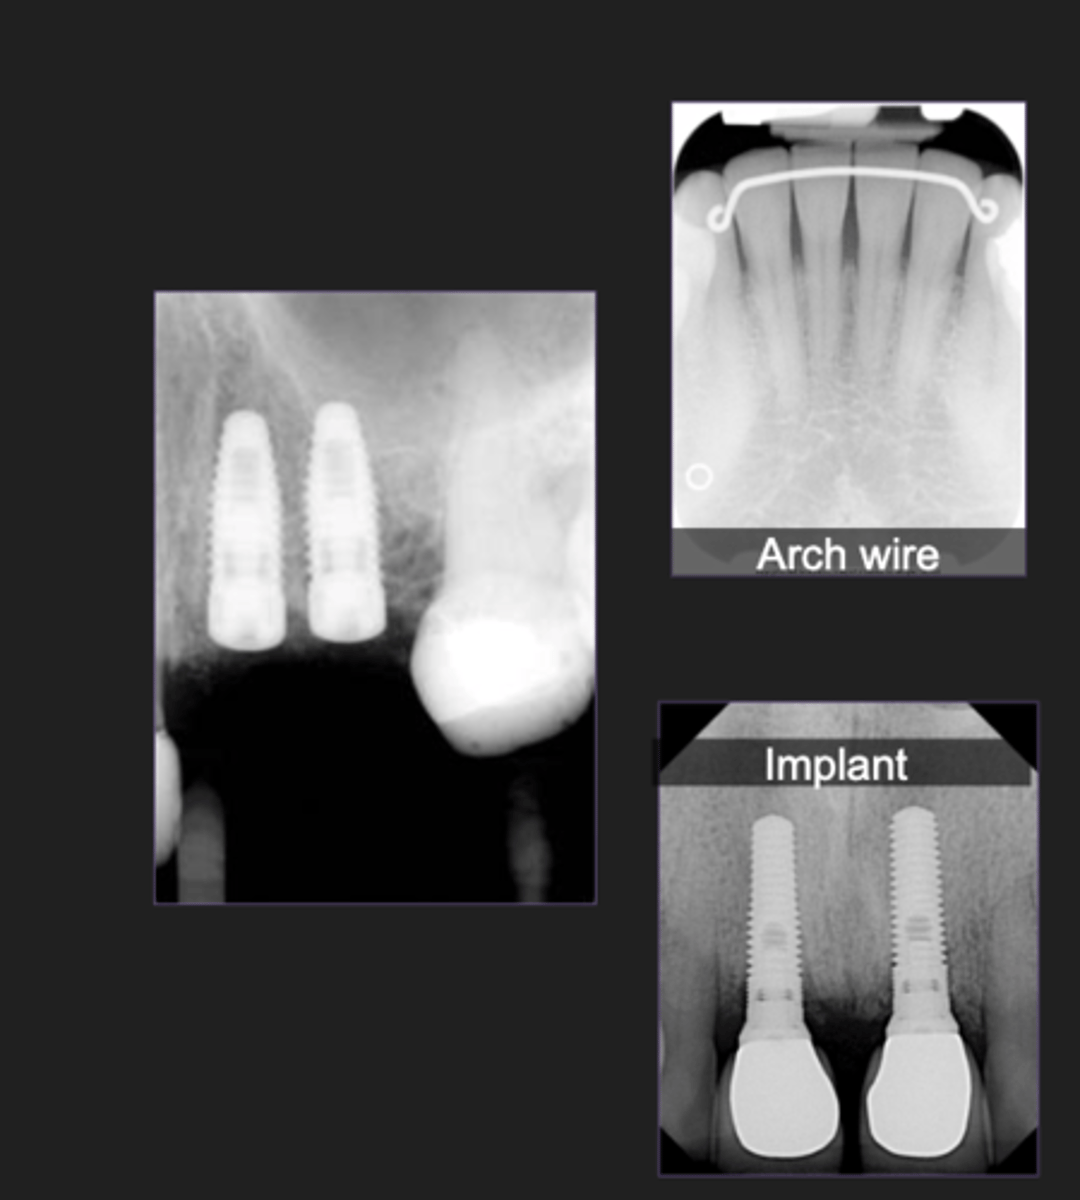

Other

- Orthodontic bands and arch wires

- Oral surgery implants